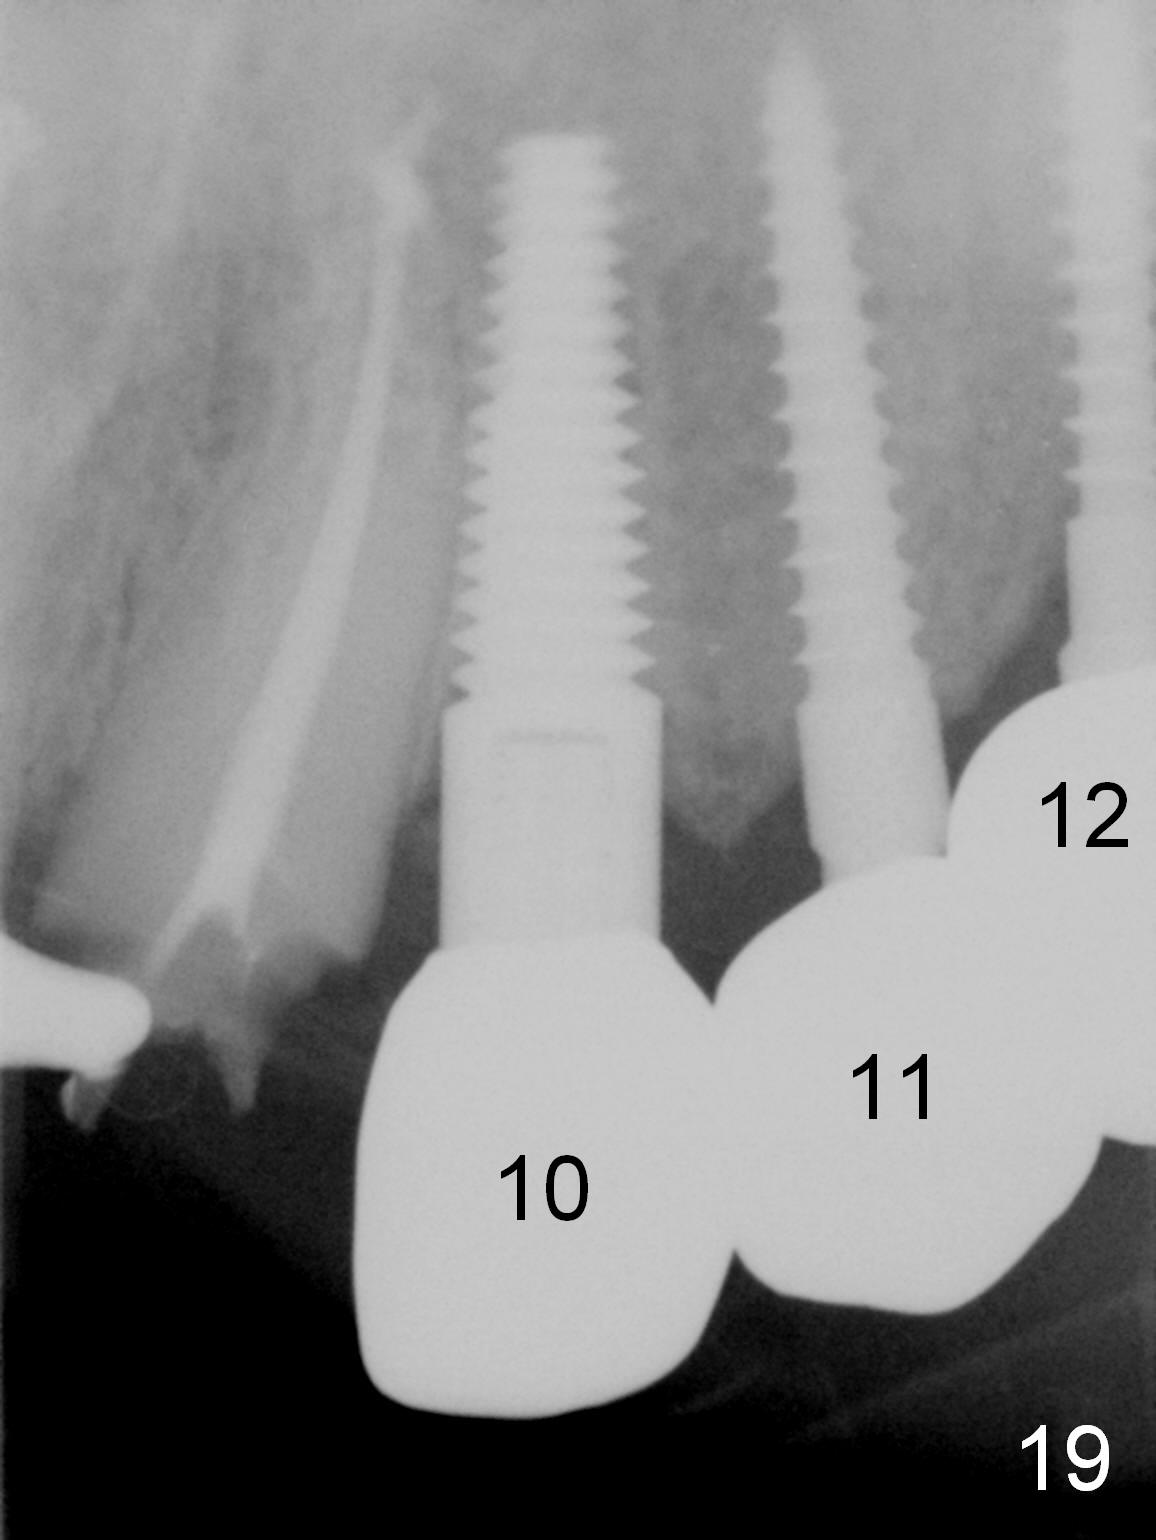

Six months post cementation, the tooth #9 becomes symptomatic. Is it possible that the implant at #10 is too close to the root of #9? It is asymptomatic after pulpotomy, but the tooth fractures equi/supragingivally. Two PAs taken while RCT show osteointegration at #10-12 (Fig.18,19). While the bone density increases at #10 regular implant, there is minimal bone loss around the 1-piece implants 13 months post cementation (18 months postop, Fig.20,21). The gingiva remains healthy 19 months post cementation (Fig.22). 76岁病人突然打电话说一个植牙牙冠松动,其实9号牙(自然牙)折裂,6,10-13号牙植牙好像没有骨质吸收(图二十三至二十五),10-13牙位牙龈健康(图二十六,行使功能五年)。9号牙牙冠重新粘固后,显示前牙深覆合,深覆盖(图二十七,二十八)。如果再次脱落需要植牙,选择一段式有助于植入和修复,因为植体和基台直径小。两段式植牙相对基台直径至少4,或者4.5毫米,前牙修复显得笨重。由于9,10牙根和植体接近,9号牙植体需要偏小而长,3x14或者15毫米(图二十九)。